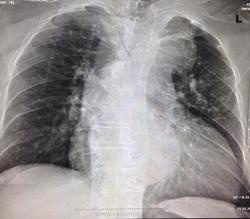

Здравствуйте! Скажите пожалуйста свое мнение по поводу снимка. Женщина 74 года. Поступила в приемное отделение с направлением из психоневрологического диспансера для исключения пневмонии. Большей информацией по больной не владею! Аневризма грудного отдела аорты?? Тысяча извинений за качество снимков!

Образование верхнего этажа передненго средостения: загрудинный зоб, лимфома, киста,тимома, аневризма восходящего отдела аорты.

Аневризмы аорты у женщины нет. Кальциноз дуги на фоне аортосклероза имеется. И возможно, с вероятностью очень большой, есть у неё дилатация полостей сердца. Но для этой цели УЗИ даст больший информационный объём.)

Справа расширено за счёт ВПВ, на верхушке справа плевральные наслоения. Аневризма аорты вполне может быть.

Вношу коррективы.Вверху- аорта. А вот но фоне сердца определяется полукруглая, интенсивная, с четким контуром тень . Наиболее выроятно - аневризма аорты.

Тут дела аотрные-деформация ( кинкинг?) ее есть в нисходящем отделе, высокое ее стояние, расширение. На боковом-"гантелька такая" На прямом круглую тень дает правый желудочек. ИМХО.

Горбатая- то она горбатая, но, мне кажется - не только... Уж как-то всё это локально выпукло, локально интенсивно

Возможно расширение есть - то бишь дилатация, но не локальное, то есть не аневризматизация.))

Надо нормально переснять, тогда и будет ясно, аорта или что-то другое.. И режим не тот, и установка. Корней и легочного рисунка толком не видно

Согласен с коллегами Миргалиной и Милой. Это аорта. Возможно без кинкинга. Высоко раположена не только аорта, но и ключицы. Хотелось бы видеть, в данном случае, и ключицы и лопатки и даже часть шеи. Подозрительная укладка, как-то снизу вверх - переснять.

Если нормально переснять - ну, чтобы с рисунком и с корнями, тогда аорту эту в прямой будет совсем не видать. Тогда все заключим спокойно мы норму.)

Спасибо большое за советы, что по делились, по этому поводу, вашим мнением!! P.S: Заключение КТ ОГК: б/о

Куда же подевалось аневризматическое расширение нисходящей части грудной аорты.